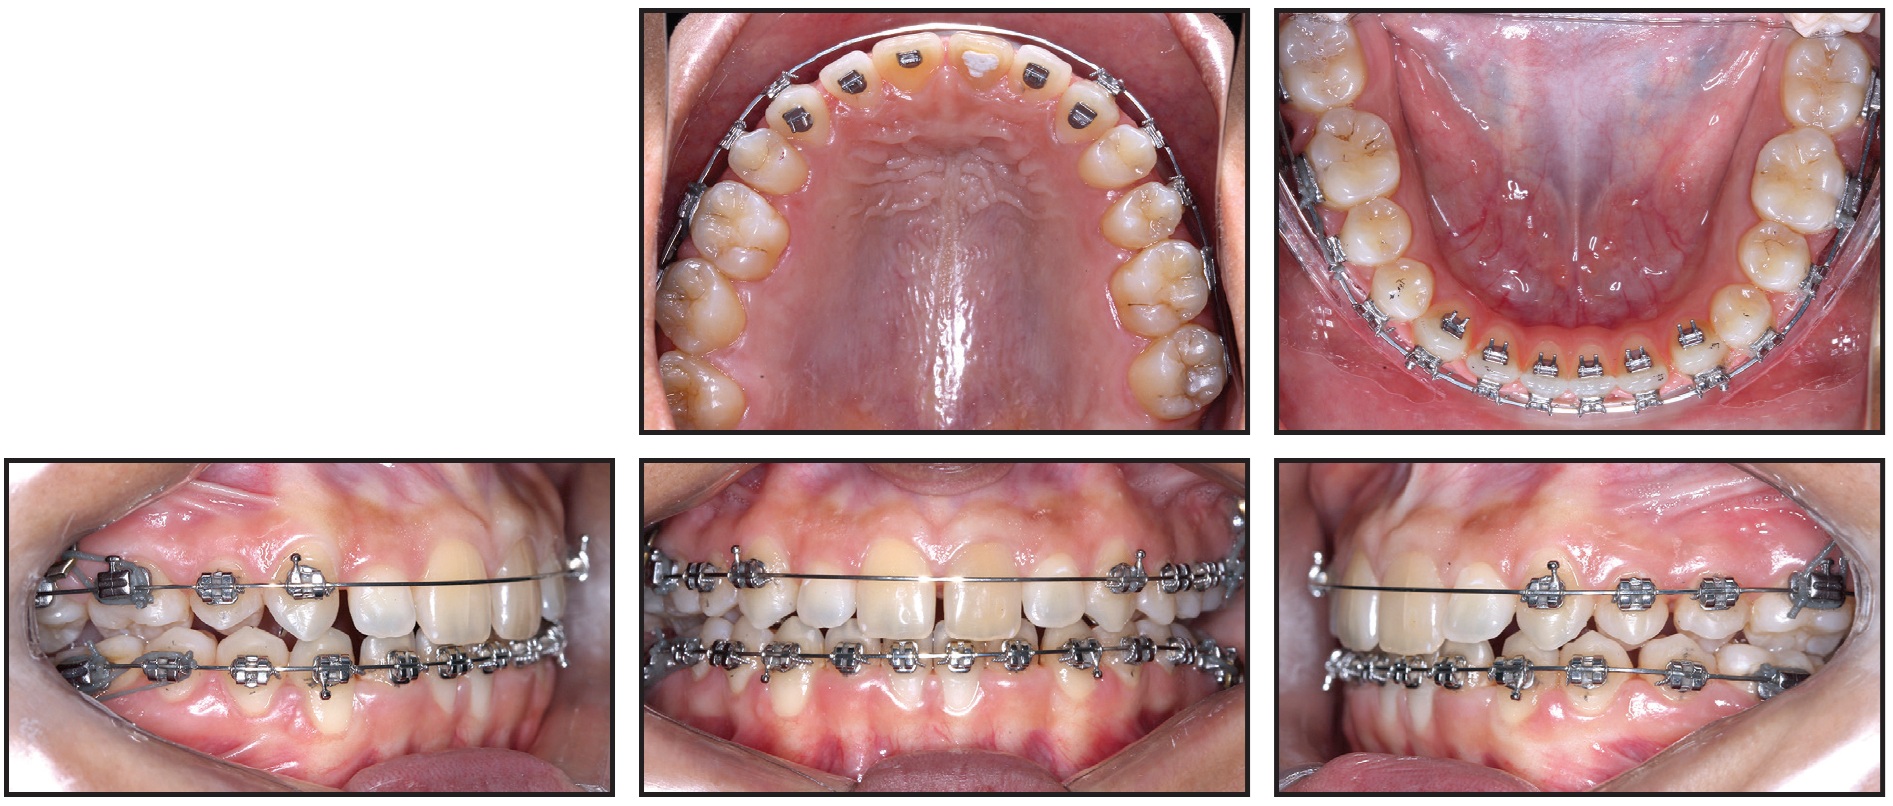

After 12 months of treatment, the miniplates were removed under local anesthesia. An .016" × .022" Blue Elgiloy*** ideal upper archwire was adapted with inset bends for the upper lateral incisors and an offset bend for the upper left first molar (Fig. 9).

Fig. 9 A. Miniplates removed after 12 months of treatment (CBCT taken before removal). Blue Elgiloy*** ideal archwires inserted in both arches, from first molar to first molar, with inset bends for upper lateral incisors and upper right first molar and offset bends for upper left and lower first molars. B. Superimposition of CBCT images taken early in treatment and after 12 months of treatment.

An inset bend was also made for the upper right first molar, considering the Class II molar relationship distal to the missing upper right first premolar. The archwire was cut distal to the upper first molars, leaving the upper right second and third molars and upper left second molar free for physiological intercuspation. An .016" × .022" Blue Elgiloy ideal wire was also adapted in the mandibular arch, with offsets only at the lower first molars. The lower second molars were not included to allow physiological occlusion with their antagonists.

Orthodontic appliances were removed after 14 months of treatment (Fig. 10). The objectives of this phase had been met with the achievement of a functional and balanced occlusion. The patient was referred for gingivoplasty, whitening, and faceting procedures on the upper central incisors.